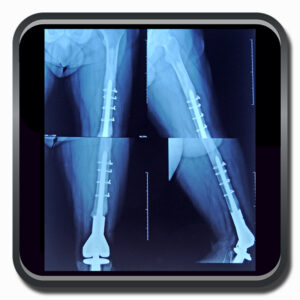

Algumas Cirurgias Complexas realizadas por profissionais da COFIB: